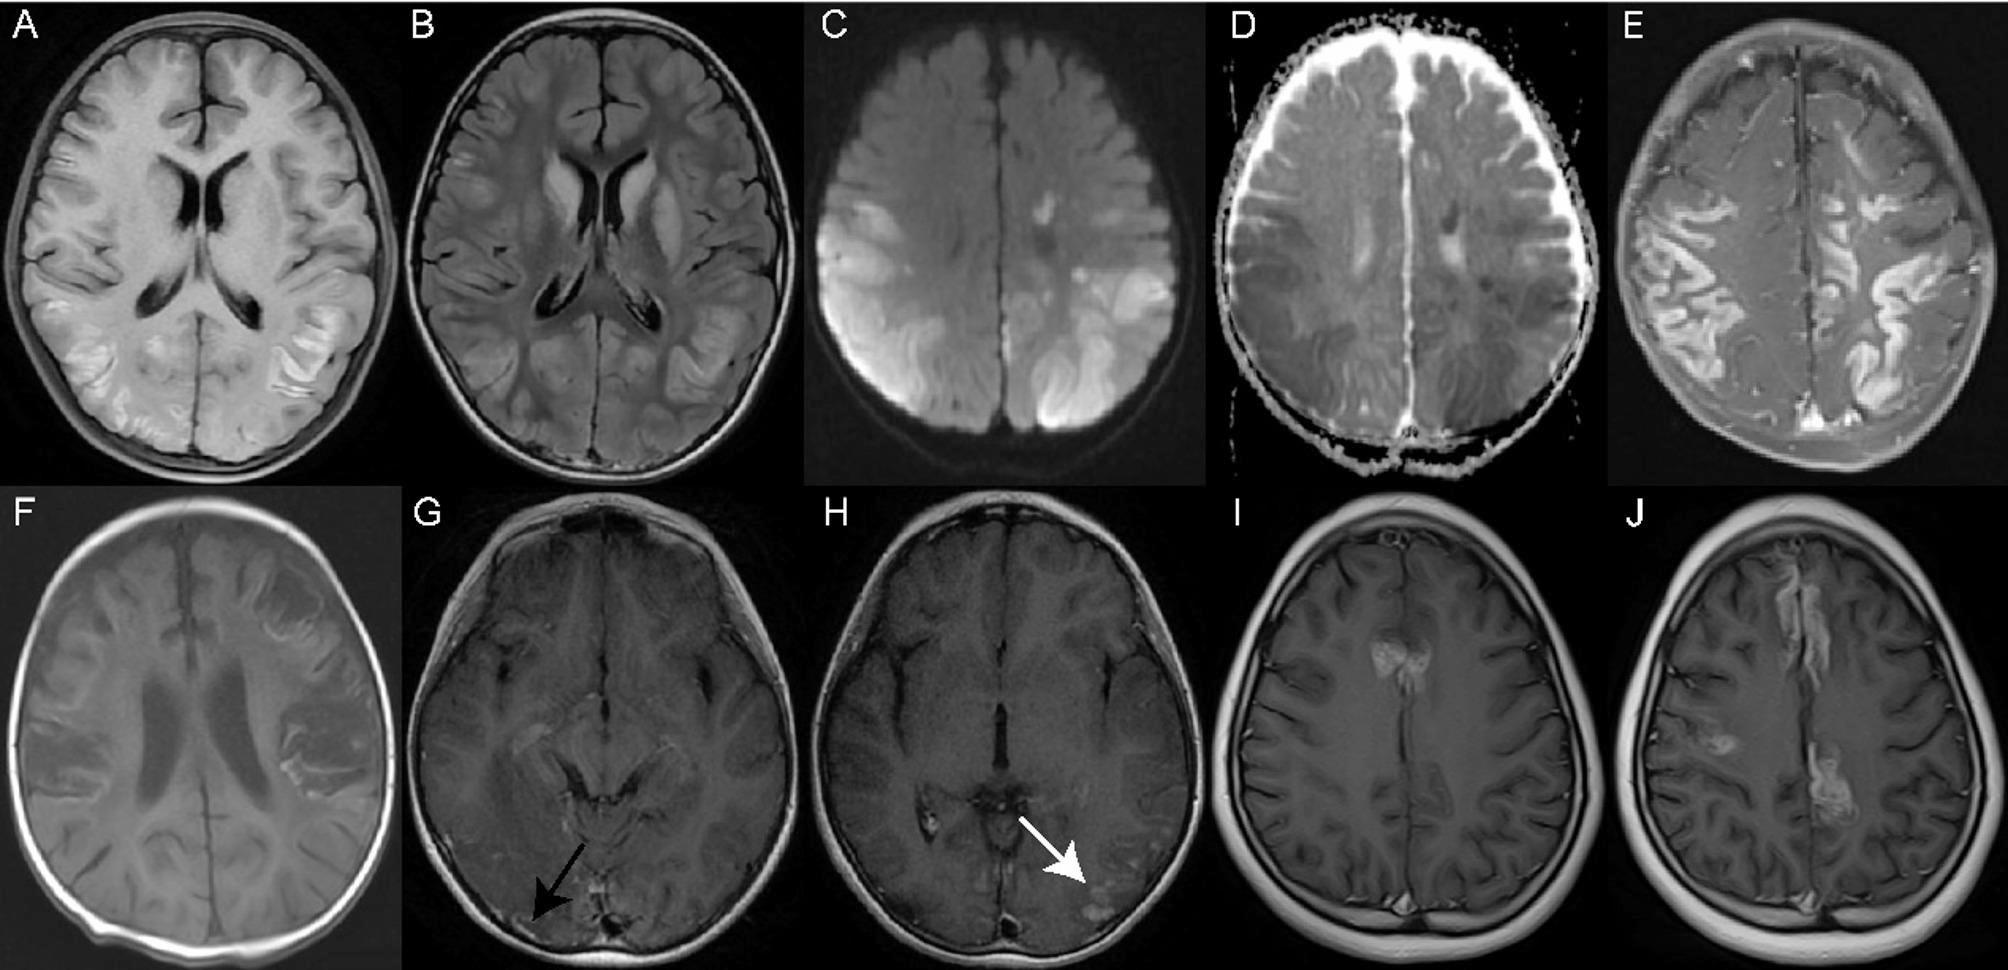

Results: Among 59 enrolled patients, causes included hypoxic-ischemic encephalopathy (HIE), hereditary and metabolic, infectious, vascular, and trauma. Seizures and consciousness changes were common symptoms. Infectious and hereditary and metabolic causes were linked to status epilepticus (P < 0.001), while vascular causes were associated with hemiplegia (P < 0.001). HIE patients had poorer prognosis (P = 0.038). MRI showed earlier hyperintensity on diffusion weighted imaging (DWI) than enhancement in T1 contrasted sequence, as well as T1 sequence and fluid attenuated inversion recovery (FLAIR). Bilateral involvement was seen in all HIE cases, while hereditary and metabolic causes often showed unilateral involvement (P < 0.001). Frontal lobe involvement was common in vascular and trauma cases (P = 0.017), and all patients with HIE exhibited involvement in the parietal and occipital lobes. While infectious cases frequently involved the insular and temporal lobes, most patients exhibited brain atrophy/encephalomalacia at follow-up. Three patients showed new CLN and two patients exhibited persistent CLN during MRI follow-up.

Abstract Image